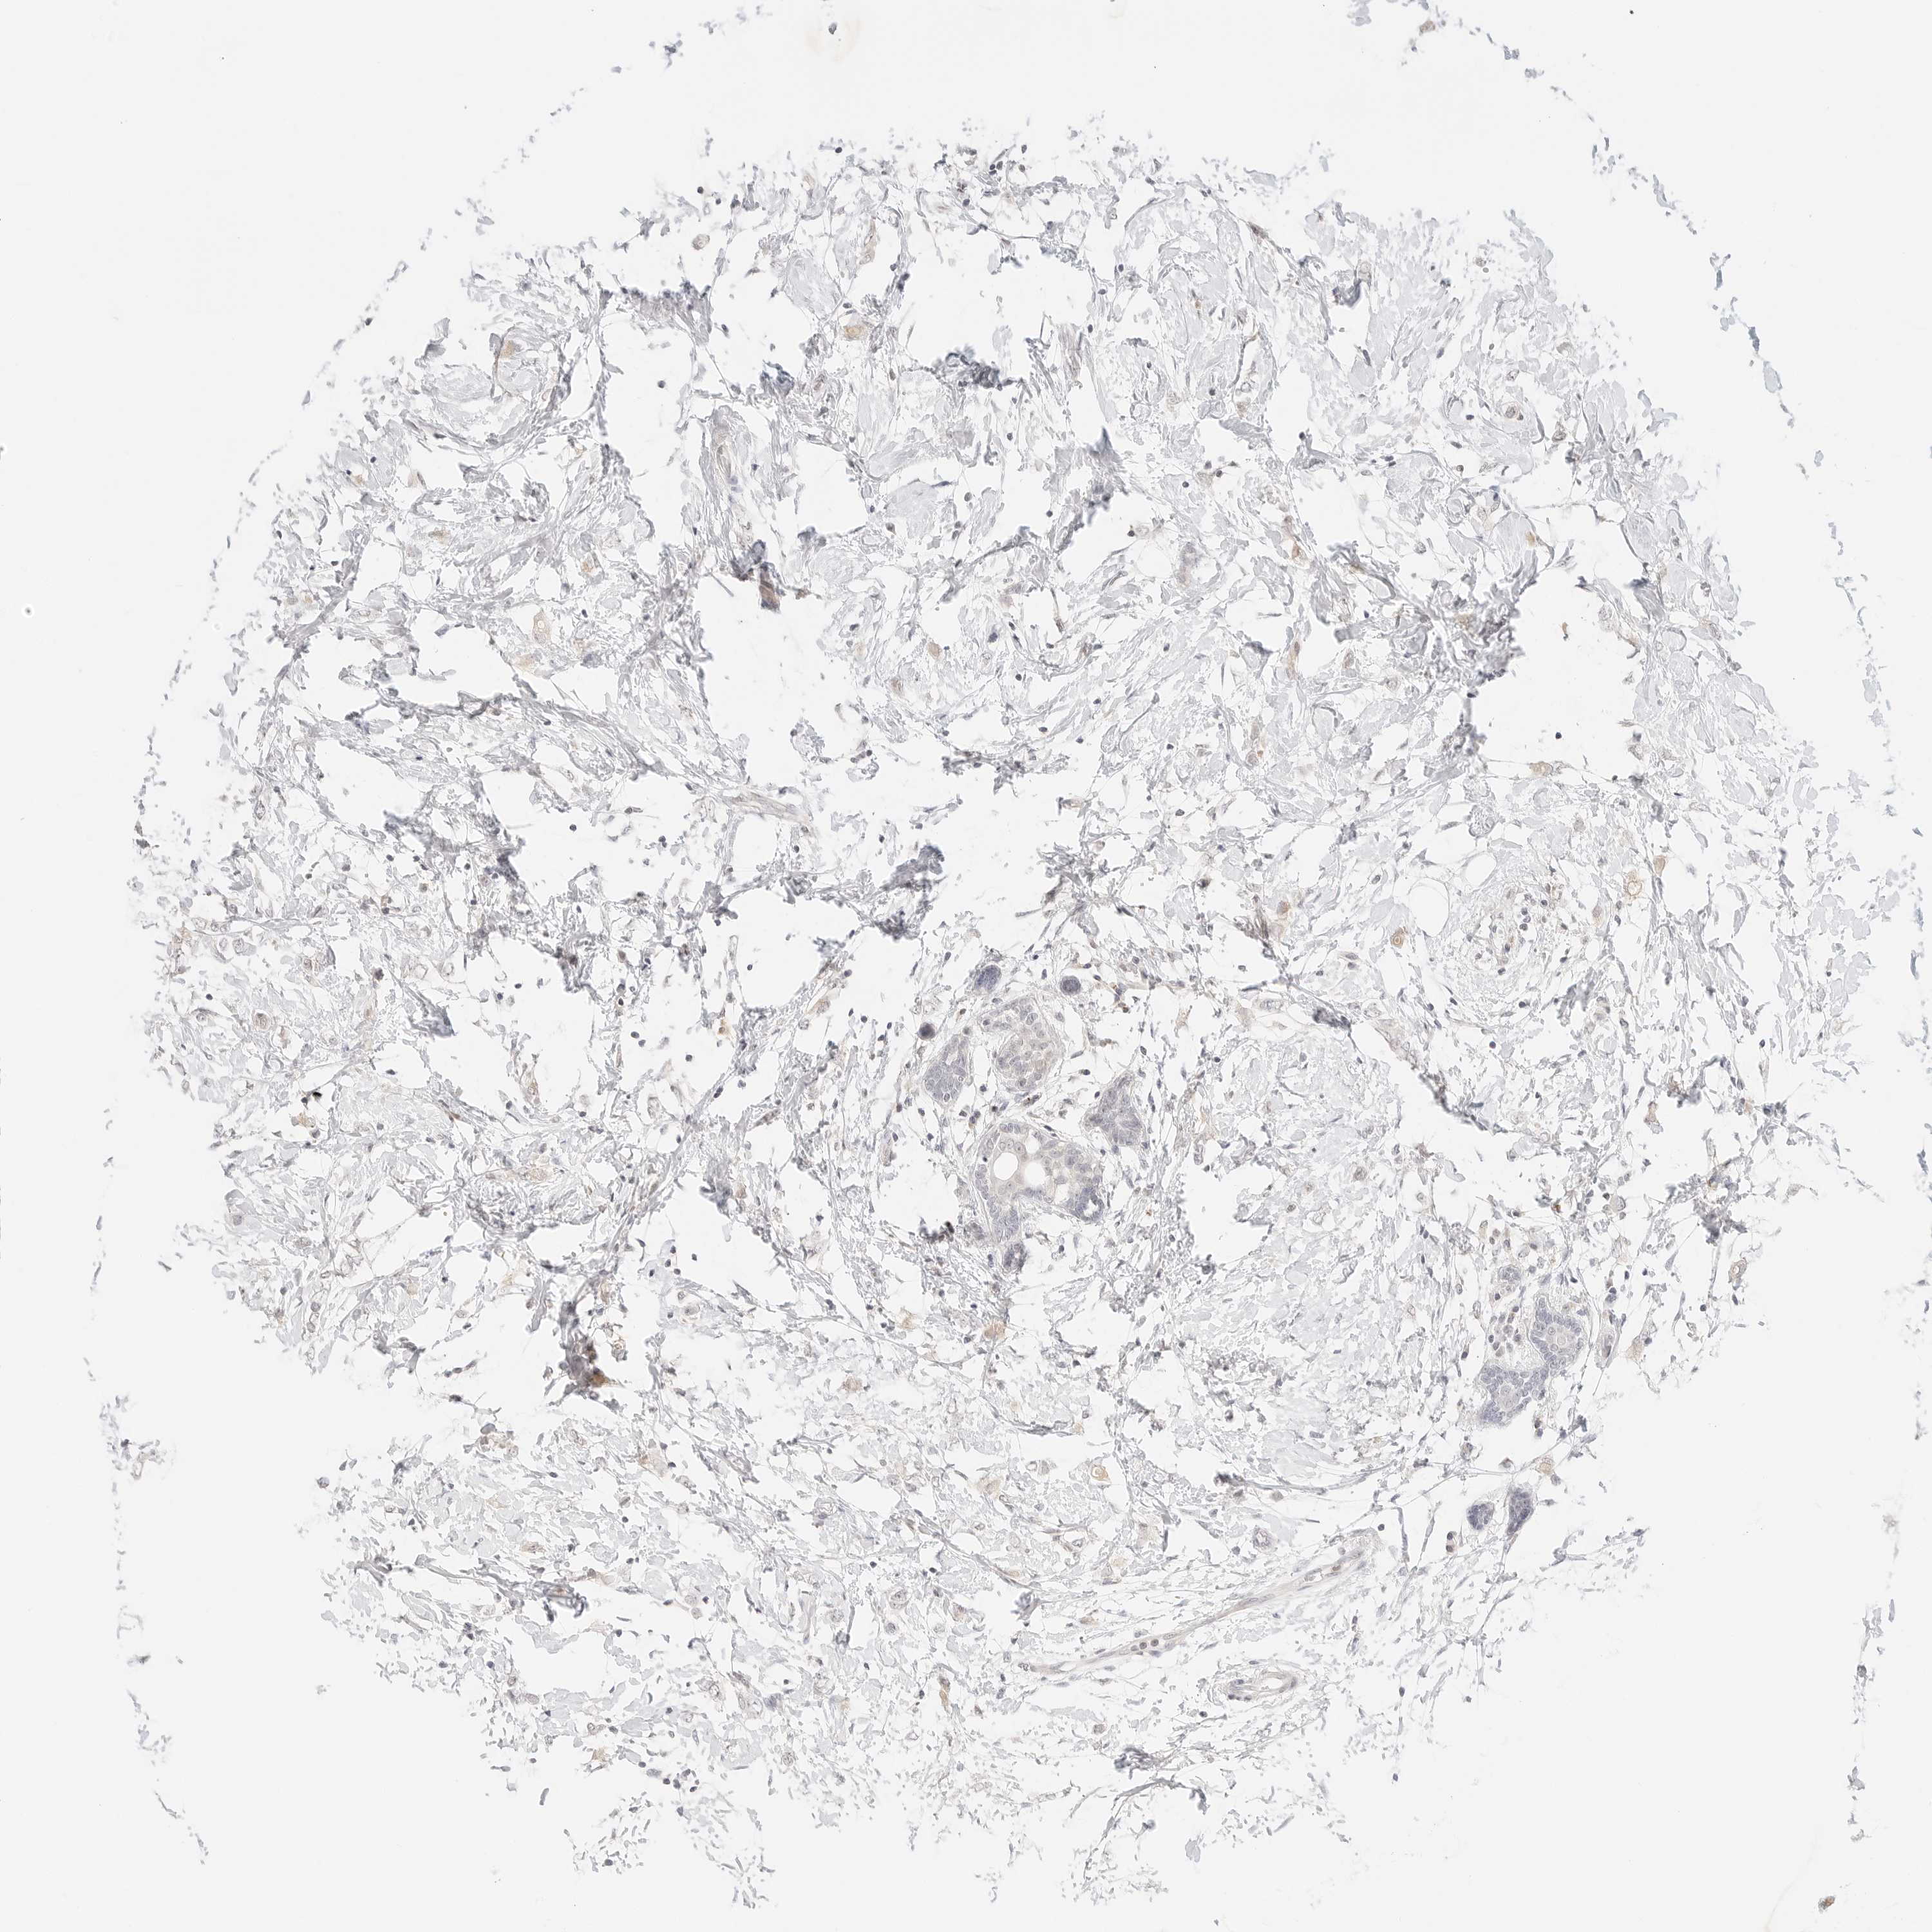

CANCER BREAST CANCER Show tissue menu

BRCA TCGA BRCA VALIDATION PROTEIN EXPRESSION